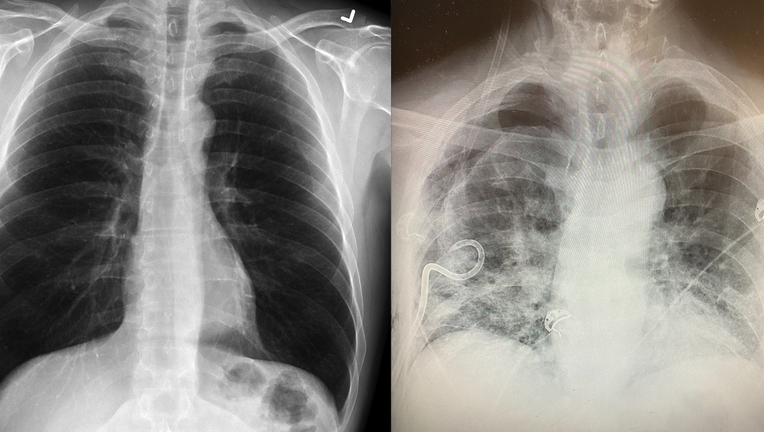

A normal, healthy lung compared to a post-COVID lung. (Credit: Dr. Brittany Bankhead-Kendall)

Dr. Brittany Bankhead-Kendall, a trauma surgeon at Texas Tech University Health Sciences Center, said she’s seeing lung scarring in some patients who have had COVID-19 that’s worse than what she sees in the lungs of people who smoke. She said she’s noticed the lung scarring in X-rays she’s taken for subsequent, unrelated health issues.

"It looks like a lot of dense scarred tissue and that extends throughout the entire lung," she explained. "Additionally, we’re seeing signs of congestion and fibrosis."